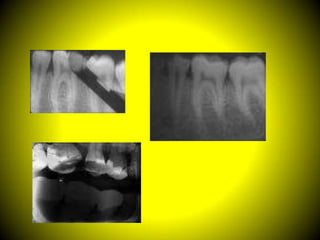

Una buena radiografía revelará el máximo de detalle en la imagen, con

una exactitud anatómica, una densidad y un contraste óptimos.

Calidad

Siempre debemos procurar obtener radiografías con la suficiente

calidad que permitan el diagnóstico porque así expondrá un máximo

de detalle para la mejor identificación de objetos pequeños.

• Mostrará de manera exacta los dientes y las estructuras

anatómicas sin distorsión ni magnificación.

• Tendrá la densidad y el contraste óptimos (características

ópticas) para rentabilizar al máximo su utilización en la

detección de enfermedad dental.